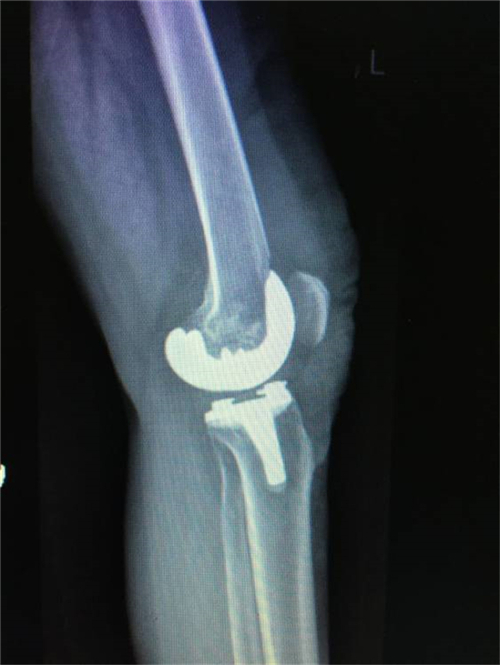

术后X线